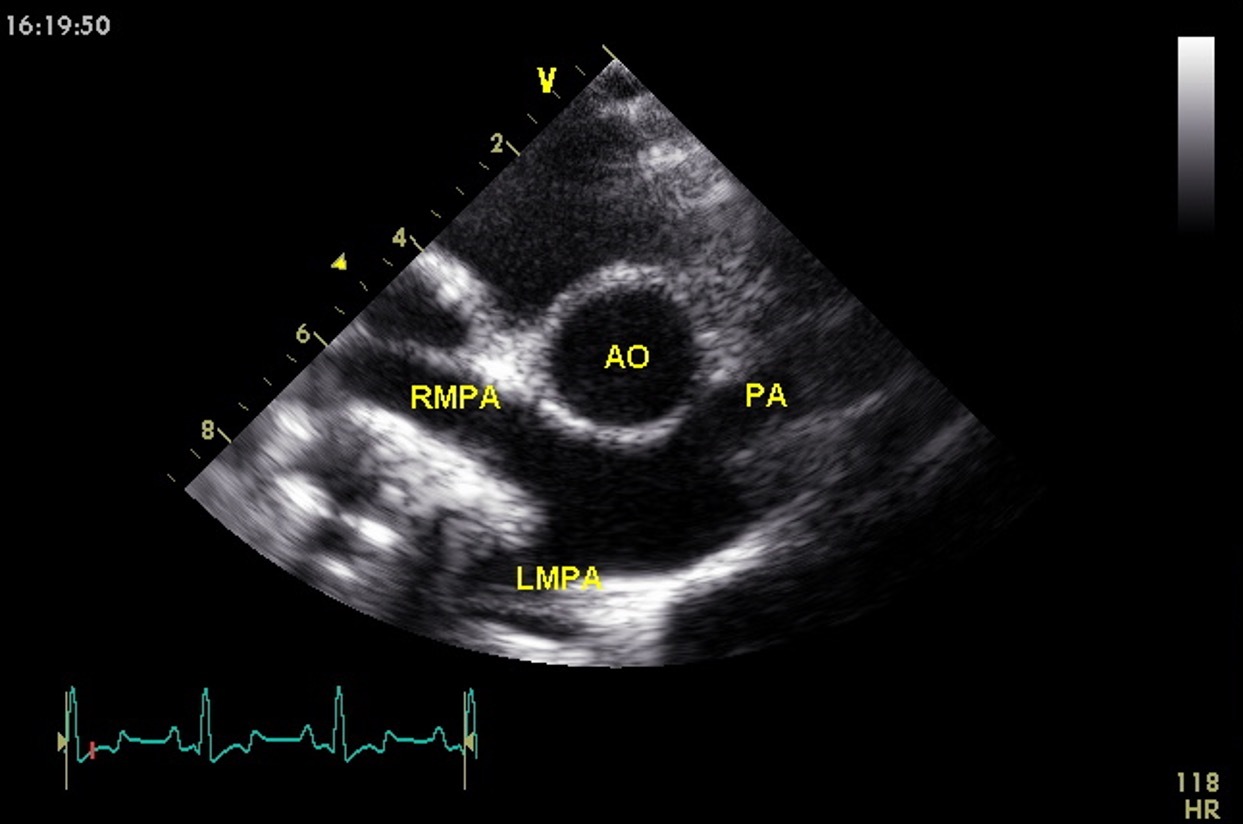

Which view is this?

Right parasternal short axis @ aortic valve